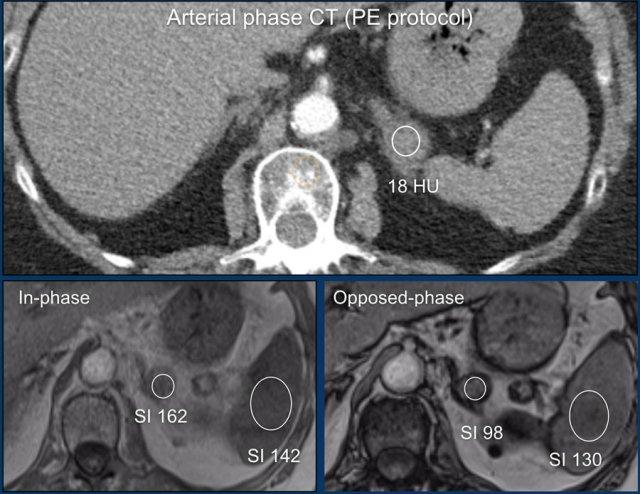

MRI được thực hiện cho tổn thương tình cờ tuyến thượng thận trái phát hiện trên CT không tiêm thuốc và pha động mạch ở bệnh nhân nam 61 tuổi có phình động mạch chủ bụng.

Trên CT không tiêm thuốc, tỷ trọng là 18 HU.

Ảnh T1 đảo pha cho thấy sự giảm tín hiệu không đồng nhất kín đáo so với ảnh đồng pha.

Lưu ý rằng chuỗi xung T1 có xóa mỡ không có giá trị trong việc phát hiện mỡ nội bào vi thể.

Tiếp tục xem các hình ảnh tiếp theo.

Vùng tăng tín hiệu trung tâm kín đáo trên chuỗi xung T1 xóa mỡ cũng tăng tín hiệu trên chuỗi xung T2W và không ngấm thuốc tương phản từ trên ảnh sau tiêm.

Sau khi so sánh với các hình ảnh CT trước đó từ nhiều năm trước, tổn thương được xác định là u tuyến phát triển chậm với xuất huyết nội u mới xảy ra.

Tổn thương tuyến thượng thận này được phát hiện tình cờ trên phim chụp CT chẩn đoán thuyên tắc phổi.

Sử dụng máy tính MRI tuyến thượng thận, tỷ số tuyến thượng thận-lách (ASR) và chỉ số cường độ tín hiệu (SI-index) có thể được đo từ các vùng quan tâm (ROI) đặt bên trong tổn thương tuyến thượng thận và lách trên cả ảnh đồng pha và ngược pha.

Dựa trên cường độ tín hiệu đo được trong các ROI đặt trên tổn thương tuyến thượng thận và lách, ASR là 0,66 (< 0,71) và SII là 39,5% (> 16,5%), cho thấy đây là một u tuyến (adenoma).